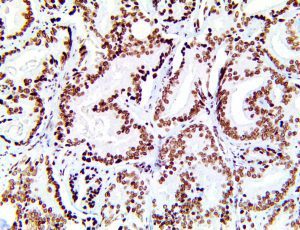

It is the ICU physician who is most likely to witness one of the deadliest manifestations of the abnormal immunological response, the cytokine storm syndrome (CSS). This response is also referred to by some as the cytokine release syndrome (CRS). CSS is characterized by continuous activation and expansion of macrophage and lymphocyte populations, which secrete large amounts of cytokines, causing the cytokine storm. This massive cytokine release is akin to hemophagocytic lymphohistiocytosis (HLH) disease, a syndrome characterized by initial unchecked and persistent activation of cytotoxic T lymphocytes and NK cells.

Clinical and laboratory manifestations of HLH include fever, enlarged liver and/or spleen, neurologic dysfunction, coagulopathy, liver dysfunction, cytopenias (i.e., low levels of erythrocytes, leukocytes, and/or platelets), hypertriglyceridemia, hyperferritinemia, hemophagocytosis, and eventually diminished NK cell activity as the immune system becomes progressively paralyzed. HLH can be familial (primary HLH) or secondary to another disease process (sHLH), such as rheumatic disease, in which it is referred to as macrophage activation syndrome (MAS, characterized by elevated ferritin).